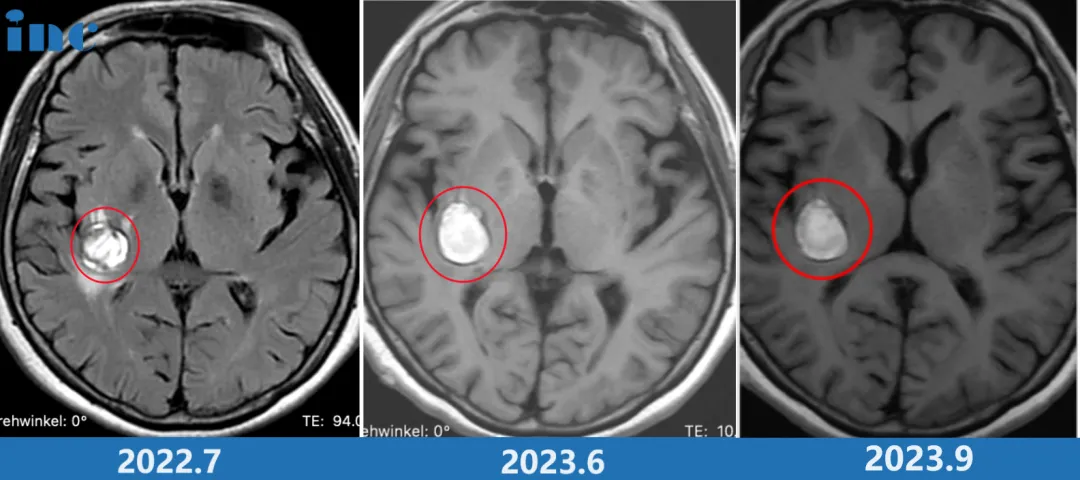

2022年,68岁的柯女士在体检中发现脑部异常,经进一步检查确诊为"右侧基底节区海绵状血管瘤伴出血",病灶尺寸15mm。初期医生建议"定期观察",加之患者本身无明显症状,因此未立即采取治疗措施。

然而疾病发展难以预测。2023年9月,柯女士症状突然加重:脚底麻木蔓延至膝盖,面部、耳部出现麻胀疼痛,复查核磁显示病灶增大。得知情况后,巴教授当晚紧急视频连线,坚定表示:"这次必须立即手术,现在是最佳时机。如果我这样返回德国,会一直放心不下。"(当时正值巴教授结束中国行程准备返回德国)